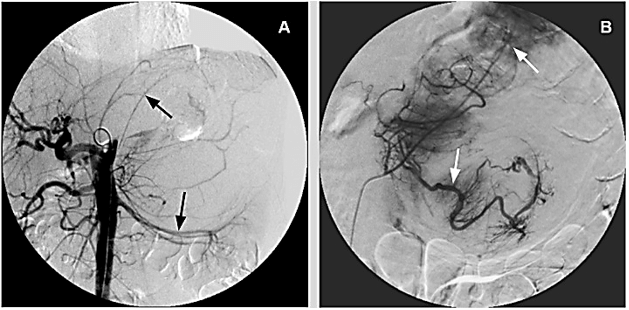

Considering size of the mass and estimated intraoperative blood loss, patient underwent preoperative abdominal angiography (Figure 2A) and subsequent transcatheter arterial embolization (TAE). The largest feeding arterial vessels, coming from adrenal and polar artery were identified and embolized by using low viscosity Precipitating Hydrophobic Injectable Liquid (Phil®) 35% agent; post TAE control enhanced optimal distribution of the embolizing agent (Figure 2B).

Figure 2: A) Preoperative Angiography: Evidence for stretched left renal artery and several pericapsular vessels. B) Post TAE control: Adequate distribution of Phil® 35% into feeding vessels.